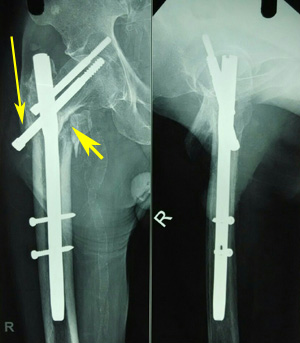

Figure 1a Varus reduction as demonstrated by medial overlap of fragments (thin arrow). Also note lateralization of entry point (thick arrow).

Figure 1b Manipulation with Steinmann pin to correct neck shaft angle as demonstrated by medial continuity and correction of overlap (arrow).

Figure 2a Radiograph showing lateralization and enlargement of the entry portal, with the nail acting as a distracting device (small arrow). Also note the varus mal-reduction (long arrow).